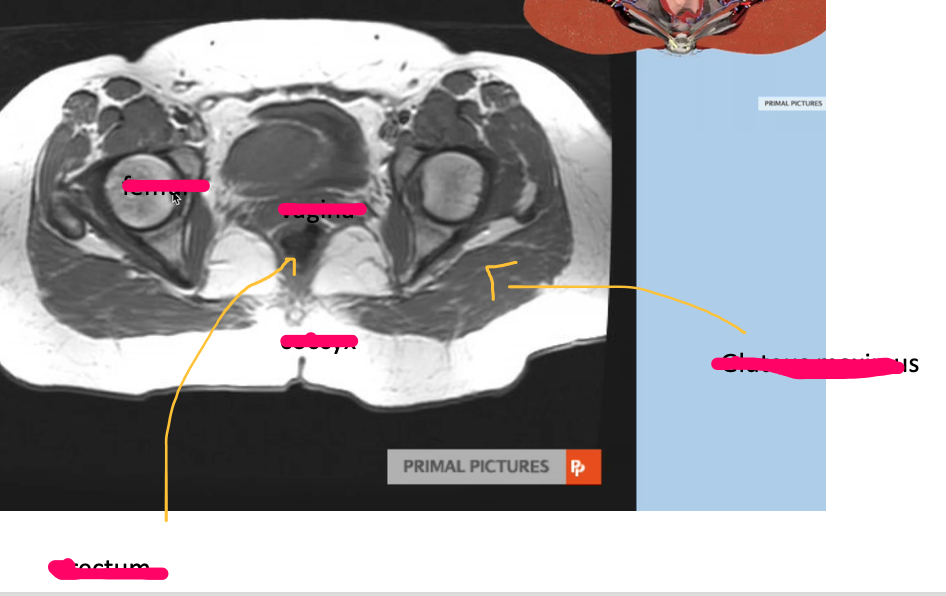

What type of imaging modality is this & fill in the blanks

MRI prostate, axial